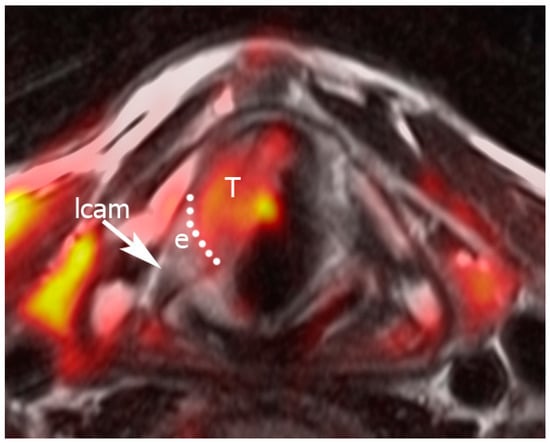

Figure 4.

Example of Pattern B, indicating fusion between a T2-weighted sequence and a diffusion-weighted imaging (DWI) image. “Hot” areas correspond to the anterior glottic tumor. A dotted line separates the tumor from the peritumoral edema. The lateral cricoarytenoid muscle is normal. Legend: e, edema; lcam, lateral cricoarytenoid muscle; T, tumor.